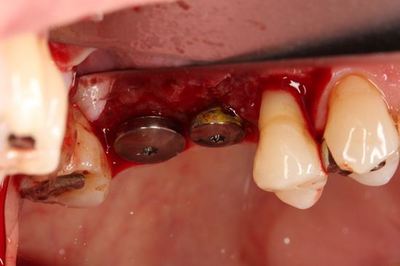

挿入ジグを外しました。インプラントネックが見えています。

ヒーリングキャップのセットを終えました。

オレンジ色に見えるのは固着防止用に用いた表面麻酔軟膏です。